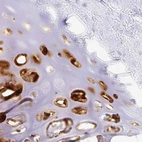

Immunohistochemical staining of human cerebral cortex, esophagus, rectum and soft tissues using Anti-ACAN antibody HPA038241 (A) shows similar protein distribution across tissues to independent antibody HPA038242 (B).